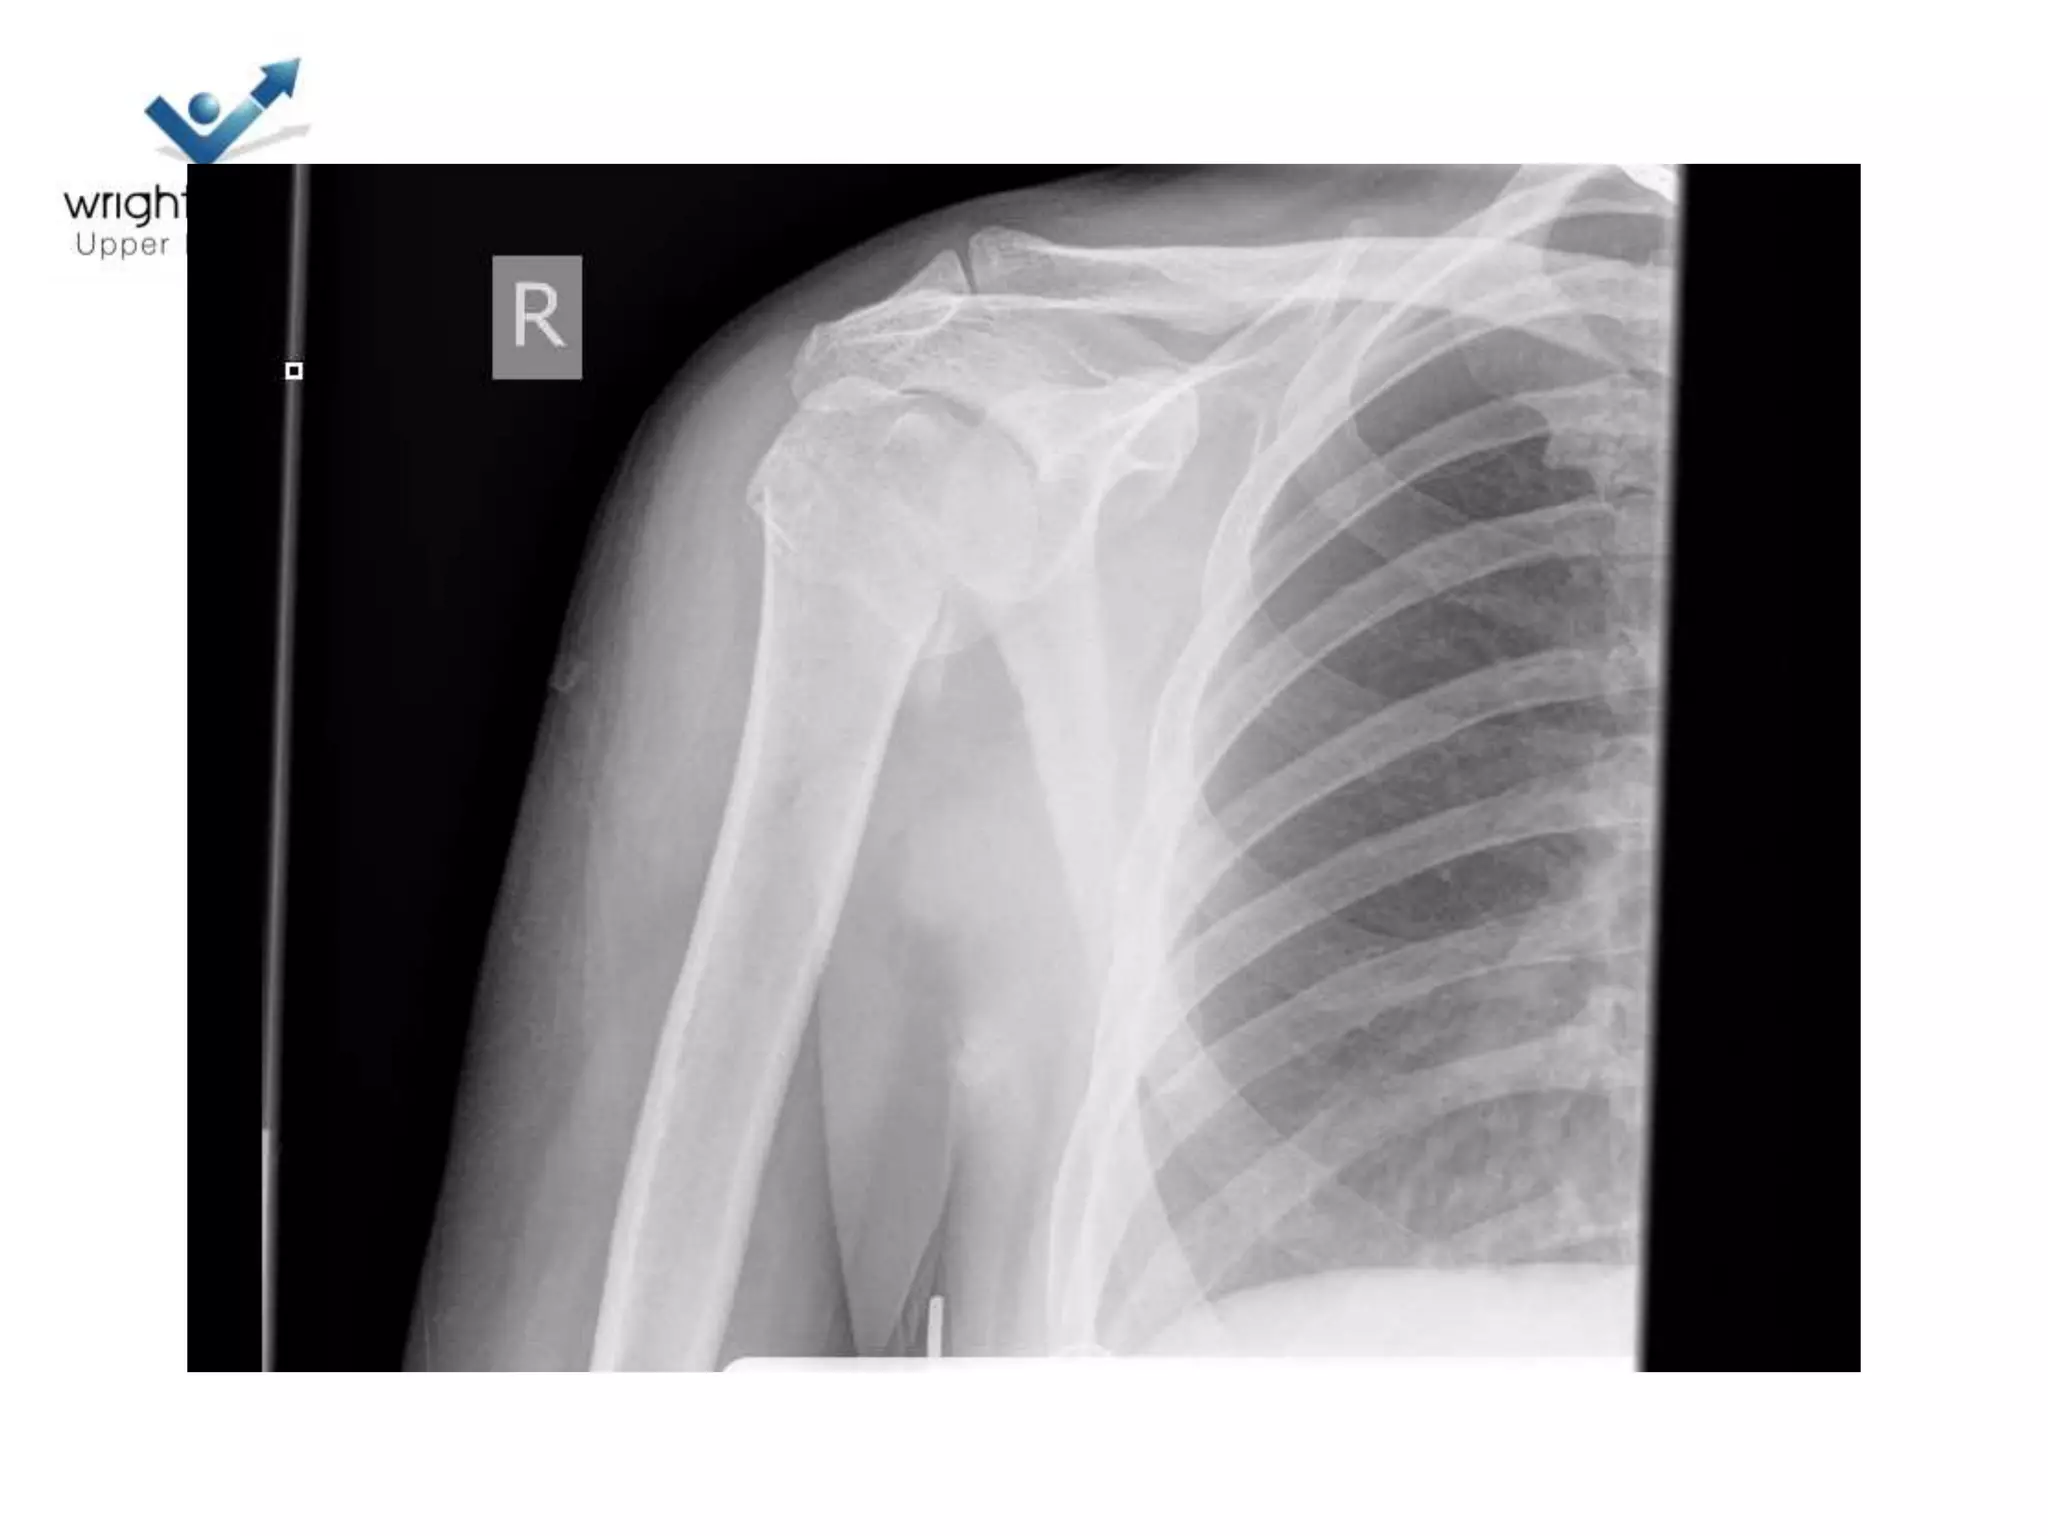

Case discussions

2 Next